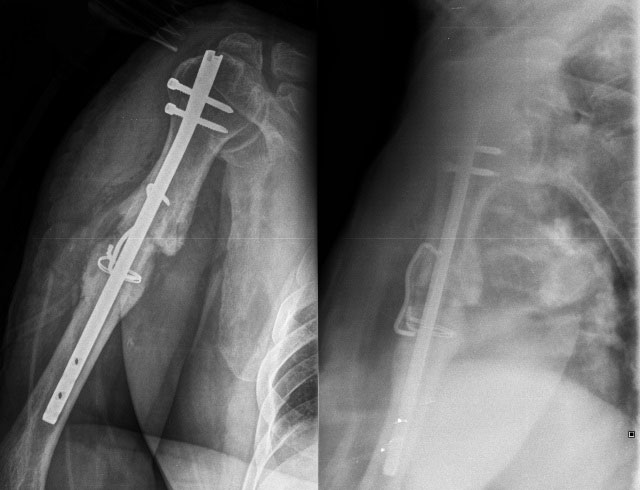

Медицинские снимки: Пластина в левом предплечье